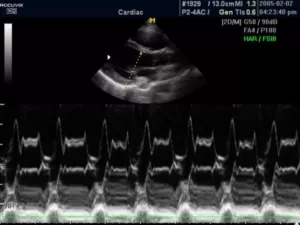

М-режим (отраженный импульсный режим)

M-mode («motion» — движение) — одномерная регистрация отраженного эхосигнала, применяющаяся в кардиологии для изучения сократительной способности миокарда, клапанного аппарата, оценки изменения размеров полостей в систолическую и диастолическую фазы.

В данном режиме оператор сканирует кардиальные структуры только вдоль одной оси. Информация о сигналах с различных глубин изображается в виде отметок различной яркости вдоль вертикальной линии на дисплее. Следующему зондированию соответствует другая линия, расположенная правее предыдущей. В ходе перемещения столбца с каждым новым сканированием записывается двухмерная М-эхограмма.

Существует несколько типов М-режима:

·      M-mode (стандартный): предполагает получение одномерного изображения;

9.jpg